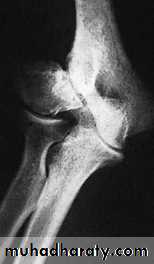

CONGENITAL DISLOCATION OF THE RADIAL HEADMay be anterior or posterior and is usually bilateral

X-rays: show that the dislocated radial head is dome-shaped